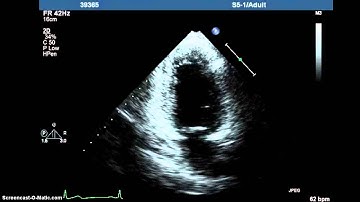

Endocardial 3D Ultrasound Segmentation using Autocontext Random Forests (MICCAI challenge 2014)